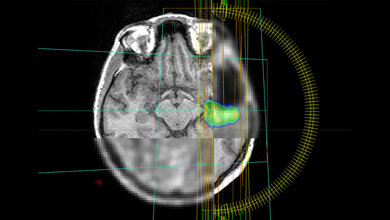

Doch auch bei der Diagnostik geht es mit Riesenschritten voran. Neben den neuen Möglichkeiten in der Bildgebung ist hier beispielsweise Liquid Biopsy ein Schlagwort. Die Nukleinsäureanalytik zum Nachweis von Tumorzellen und Tumor-DNA sorgt für Furore.